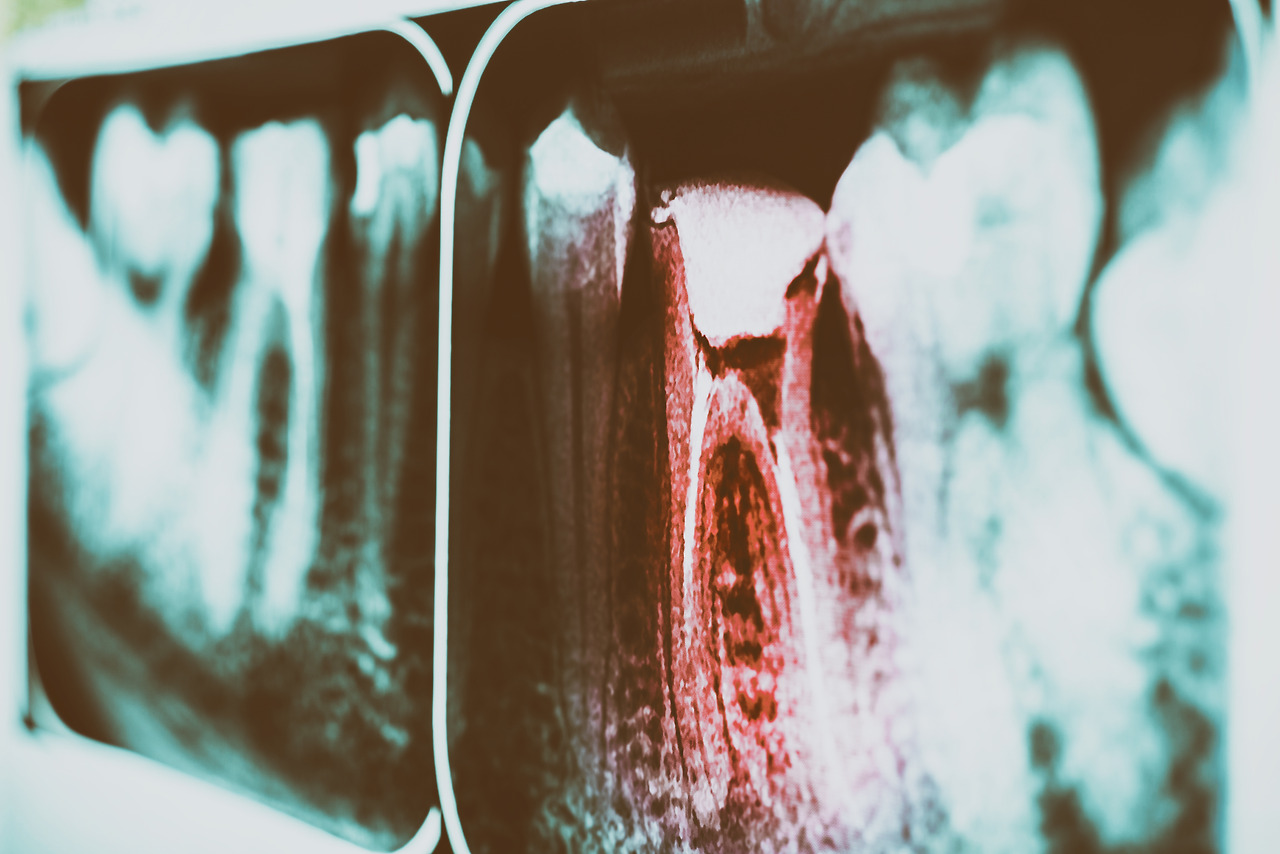

임플란트 주위염이란 임플란트 주변의 잇몸과 잇몸뼈에 발생하는 염증으로, 자연치아에서 발생하는 잇몸에서 피가 나고 잇몸뼈가 흡수되는 감염성 질환인 치주염과 같다고 할 수 있습니다.

치아와 잇몸뼈 사이에 있는 자연치아의 치주인대는 저작기능 시 완충작용 및 세균에 대한 저항성을 높이는 역할을 하는데, 임플란트에는 이런 치주인대가 없어 음식물 찌꺼기나 치태, 치석으로 인한 염증이 생길 확률이 더욱 높아지고 염증 반응도 빠르게 일어납니다.

하지만 신경이 없어 임플란트 주위에 염증이 생겼을 때에도 통증을 잘 느끼지 못해 임플란트 주위염이 상당히 진행된 후에 발견되는 경우가 많죠.